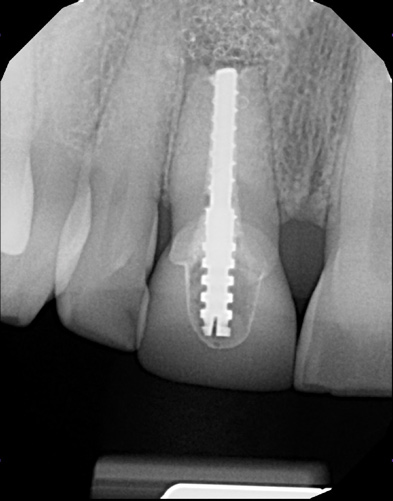

(6.) Pretreatment periapical radiograph.

Figure 6

A 56-year-old female patient was referred for the evaluation of tooth No. 8 (Figure 4 and Figure 5). A periapical radiograph indicated that the tooth had undergone apicoectomy and received an excessively long post (Figure 6), and a cone-beam computed tomography (CBCT) scan of the site revealed a lack of buccal plate bone (Figure 7).